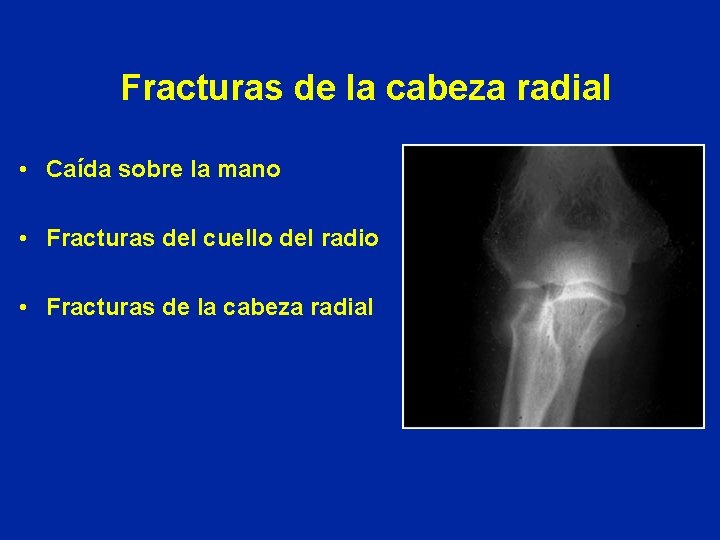

Fracturas de la cabeza radial • Caída sobre la mano • Fracturas del cuello del radio • Fracturas de la cabeza radial